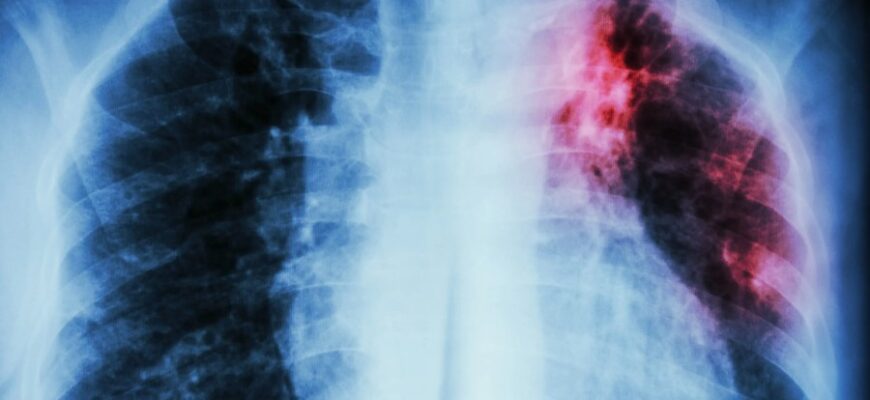

- Рентгенографія легень. Дає змогу побачити зміни у легенях, характерні для туберкульозу.